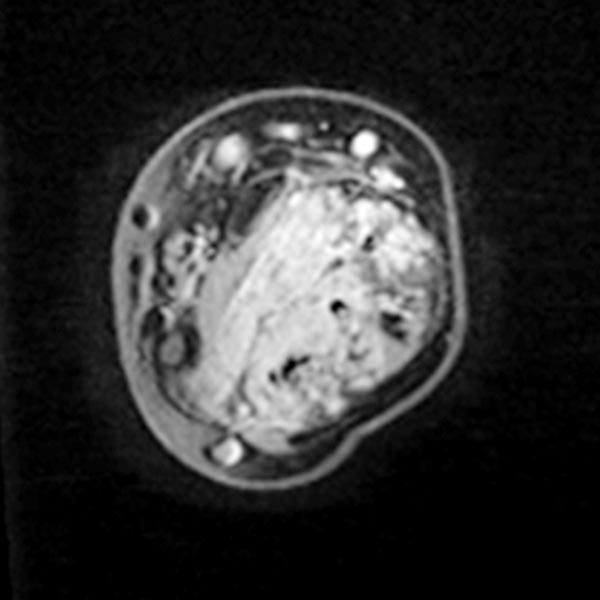

Axiale T1-gewichtete, fettunterdrückte KM-unterstützte Sequenz mittlerer Unterarm.

Die venöse Malformation reichert Kontrastmittel an innerhalb der durchsetzten Muskulatur.

Die Gefäßlumina der venösen Malformation sind jedoch relativ klein, es finden sich keine größeren tubulären Anteile.